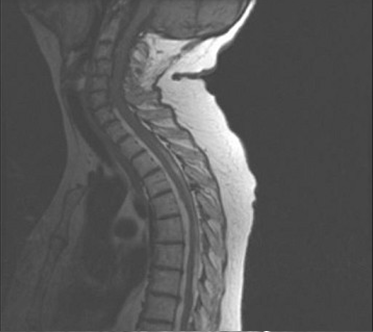

180、单项选择题

女,68岁,头部剧痛伴左上肢无力半月余,近两天发展为双下肢截瘫,请结合影像学检查,选出最可能的诊断()

A.脊髓空洞症

B.椎管内血肿

C.硬膜外脓肿

D.脊膜膨出

E.脊膜瘤

181、问答题 髓外硬脊膜内肿瘤的临床特点是什么?